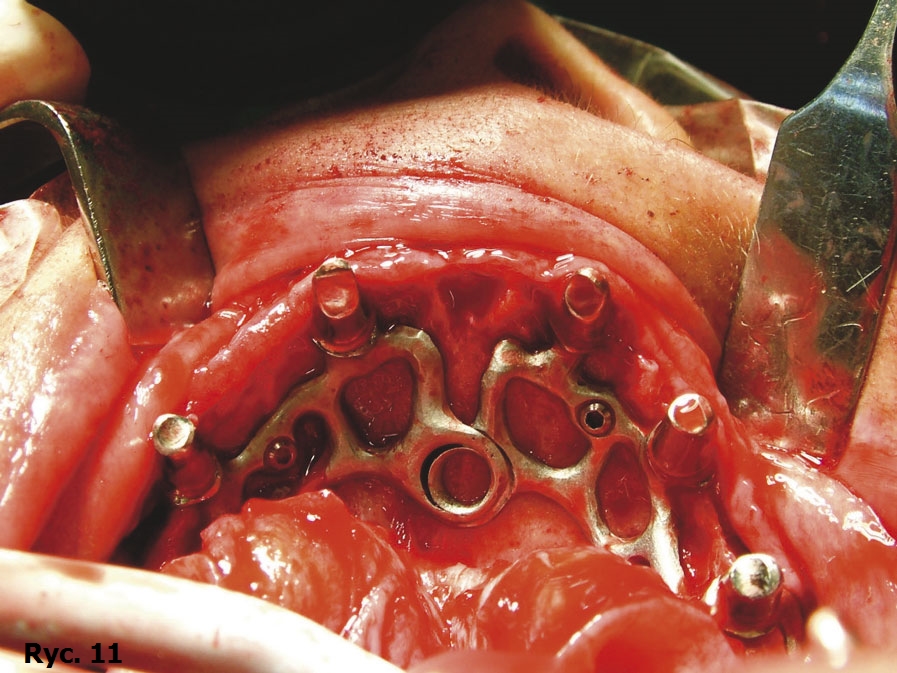

Wyniki badania TK oraz model stereolitograficzny pozwoliły na wykonanie dwóch oddzielnych siatek wszczepu podokostnowego w obrębie łuku górnego (ryc. 9), które zostały później wszczepione (ryc. 10) oraz połączone ze sobą, aby wspólnie przenosić siły żucia (ryc. 11), stanowiąc podparcie dla estetycznego uzupełnienia protetycznego stałego (ryc. 12, 13). Zabieg chirurgiczny przebiegł bez powikłań. Przysłana z Karaibów kartka pocztowa z trzema słowami „drugi miesiąc miodowy” potwierdziła, że cała wykonana przez lekarza praca zakończyła się sukcesem.